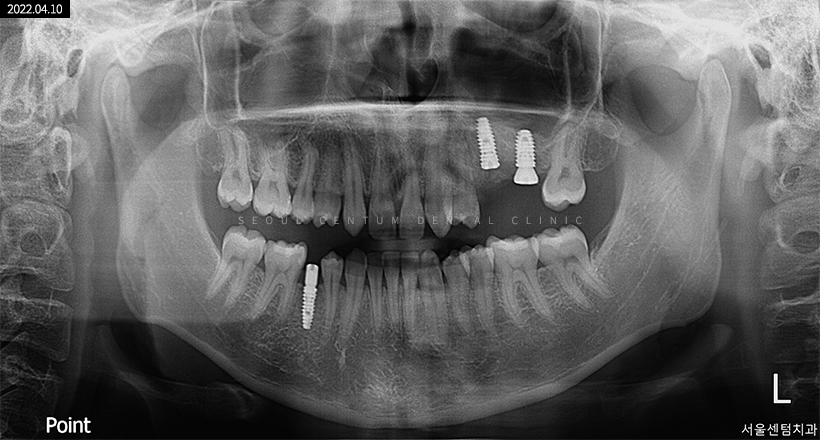

실제로 저희 치과에 내원해 주신 한 환자분의 파노라마 엑스레이 사진입니다.

임플란트 1차 과정

✔ 1차 수술 과정은 임플란트의 핵심 과정이라고 할 수 있을 정도로 가장 중요합니다. ✔

잇몸뼈에 픽스처를 이식 후 잇몸을 덮어서 잇몸뼈와 픽스처의 골융합이 이루어지게끔 만듭니다. 이 과정은 약 30분~1시간이 소요되고 임플란트를 해야 하는 치아가 많을수록 진행 시간은 더 늘어날 수 있습니다.

실밥은 잇몸이 어느 정도 아물면(약 일주일 소요) 제거하는데, 일주일 후에도 실밥을 제거하지 않으면 실밥 사이로 음식물이 끼면서 잇몸 질환이 발생할 수 있으니 잊지 말고 제거 받으시길 바랍니다.